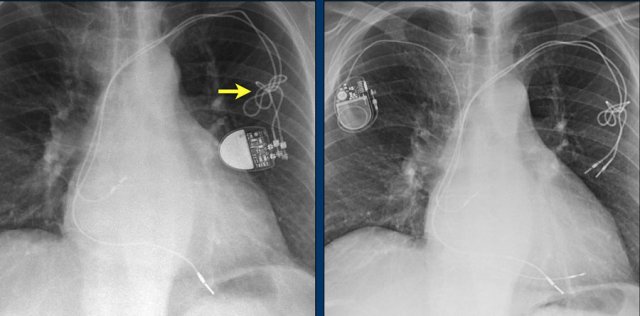

Here a patient with a normally placed ICD on the left image.

Months later there was malfunction due to ICD box and lead rotation (yellow arrow) and retraction (white arrow).

Here another patient with the Twiddler's syndrome.

Notice curling of the lead near the pacemaker and at the tip in the right ventricle (arrows).